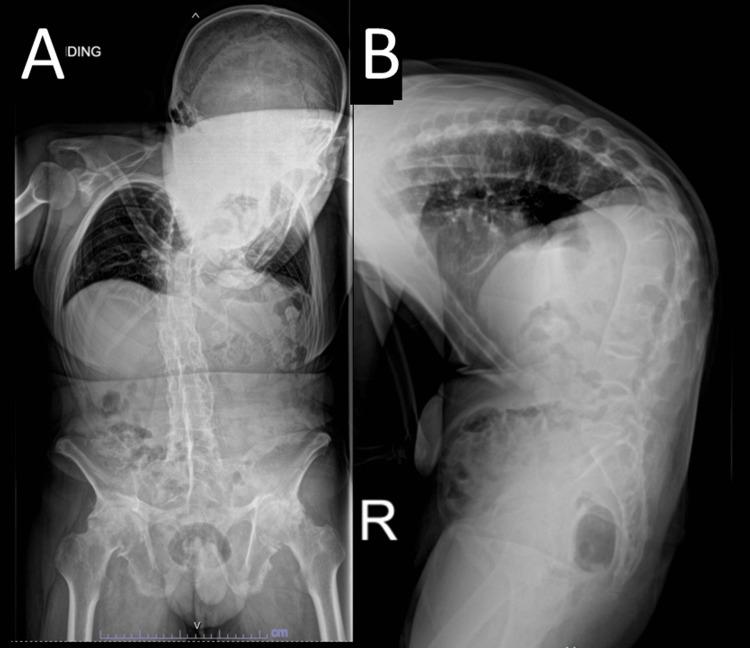

从低头看地到昂首向前:一例强直性脊柱炎患者的严重脊柱后凸病例

Ankylosing spondylitis (AS) is a chronic inflammatory disorder characterized by progressive spinal stiffness and deformity, primarily affecting the sacroiliac joints, spine, and pelvis. In advanced cases, untreated AS can lead to severe kyphosis, resulting in debilitating functional impairment and a significantly reduced quality of life. We present a case of a patient with a fixed thoracolumbar kyphotic deformity that severely affected his daily function. He underwent an L1 and L4 pedicle subtraction osteotomy (PSO) and posterior spinal instrumentation. This case highlights the challenges associated with correcting rigid spinal deformities in AS patients, where surgical intervention is often the only option to restore function and quality of life. Despite the high risk of complications, advancements in surgical techniques and implants have improved outcomes even in the most complex cases. Detailed preoperative planning, precise surgical execution, and cautious postoperative management are crucial for successful outcomes in such high-risk procedures.

强直性脊柱炎(AS)是一种慢性炎症性疾病,其特征为进行性脊柱僵硬和畸形,主要影响骶髂关节、脊柱和骨盆。在晚期病例中,未经治疗的AS可导致严重驼背,造成功能障碍并显著降低生活质量。我们报告一例患有固定性胸腰椎后凸畸形的患者,该畸形严重影响其日常功能。他接受了L1和L4椎体截骨术(PSO)及后路脊柱内固定术。该病例突出了AS患者矫正僵硬脊柱畸形所面临的挑战,在这种情况下手术干预往往是恢复功能和生活质量的唯一选择。尽管并发症风险很高,但手术技术和植入物的进步即使在最复杂的病例中也改善了治疗效果。详细的术前规划、精确的手术操作以及谨慎的术后管理对于此类高风险手术的成功结果至关重要。